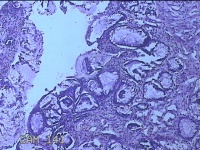

肛门肿物

性别

男

年龄

40岁

临床诊断

混合痔

一般病史

反复肛门肿物突出15年。

标本名称

大体所见

灰白暗红色肿物0.7x0.5x0.2cm一个,表面糜烂。

脱水、透明,浸蜡、脱蜡效果不佳,制片质量差。